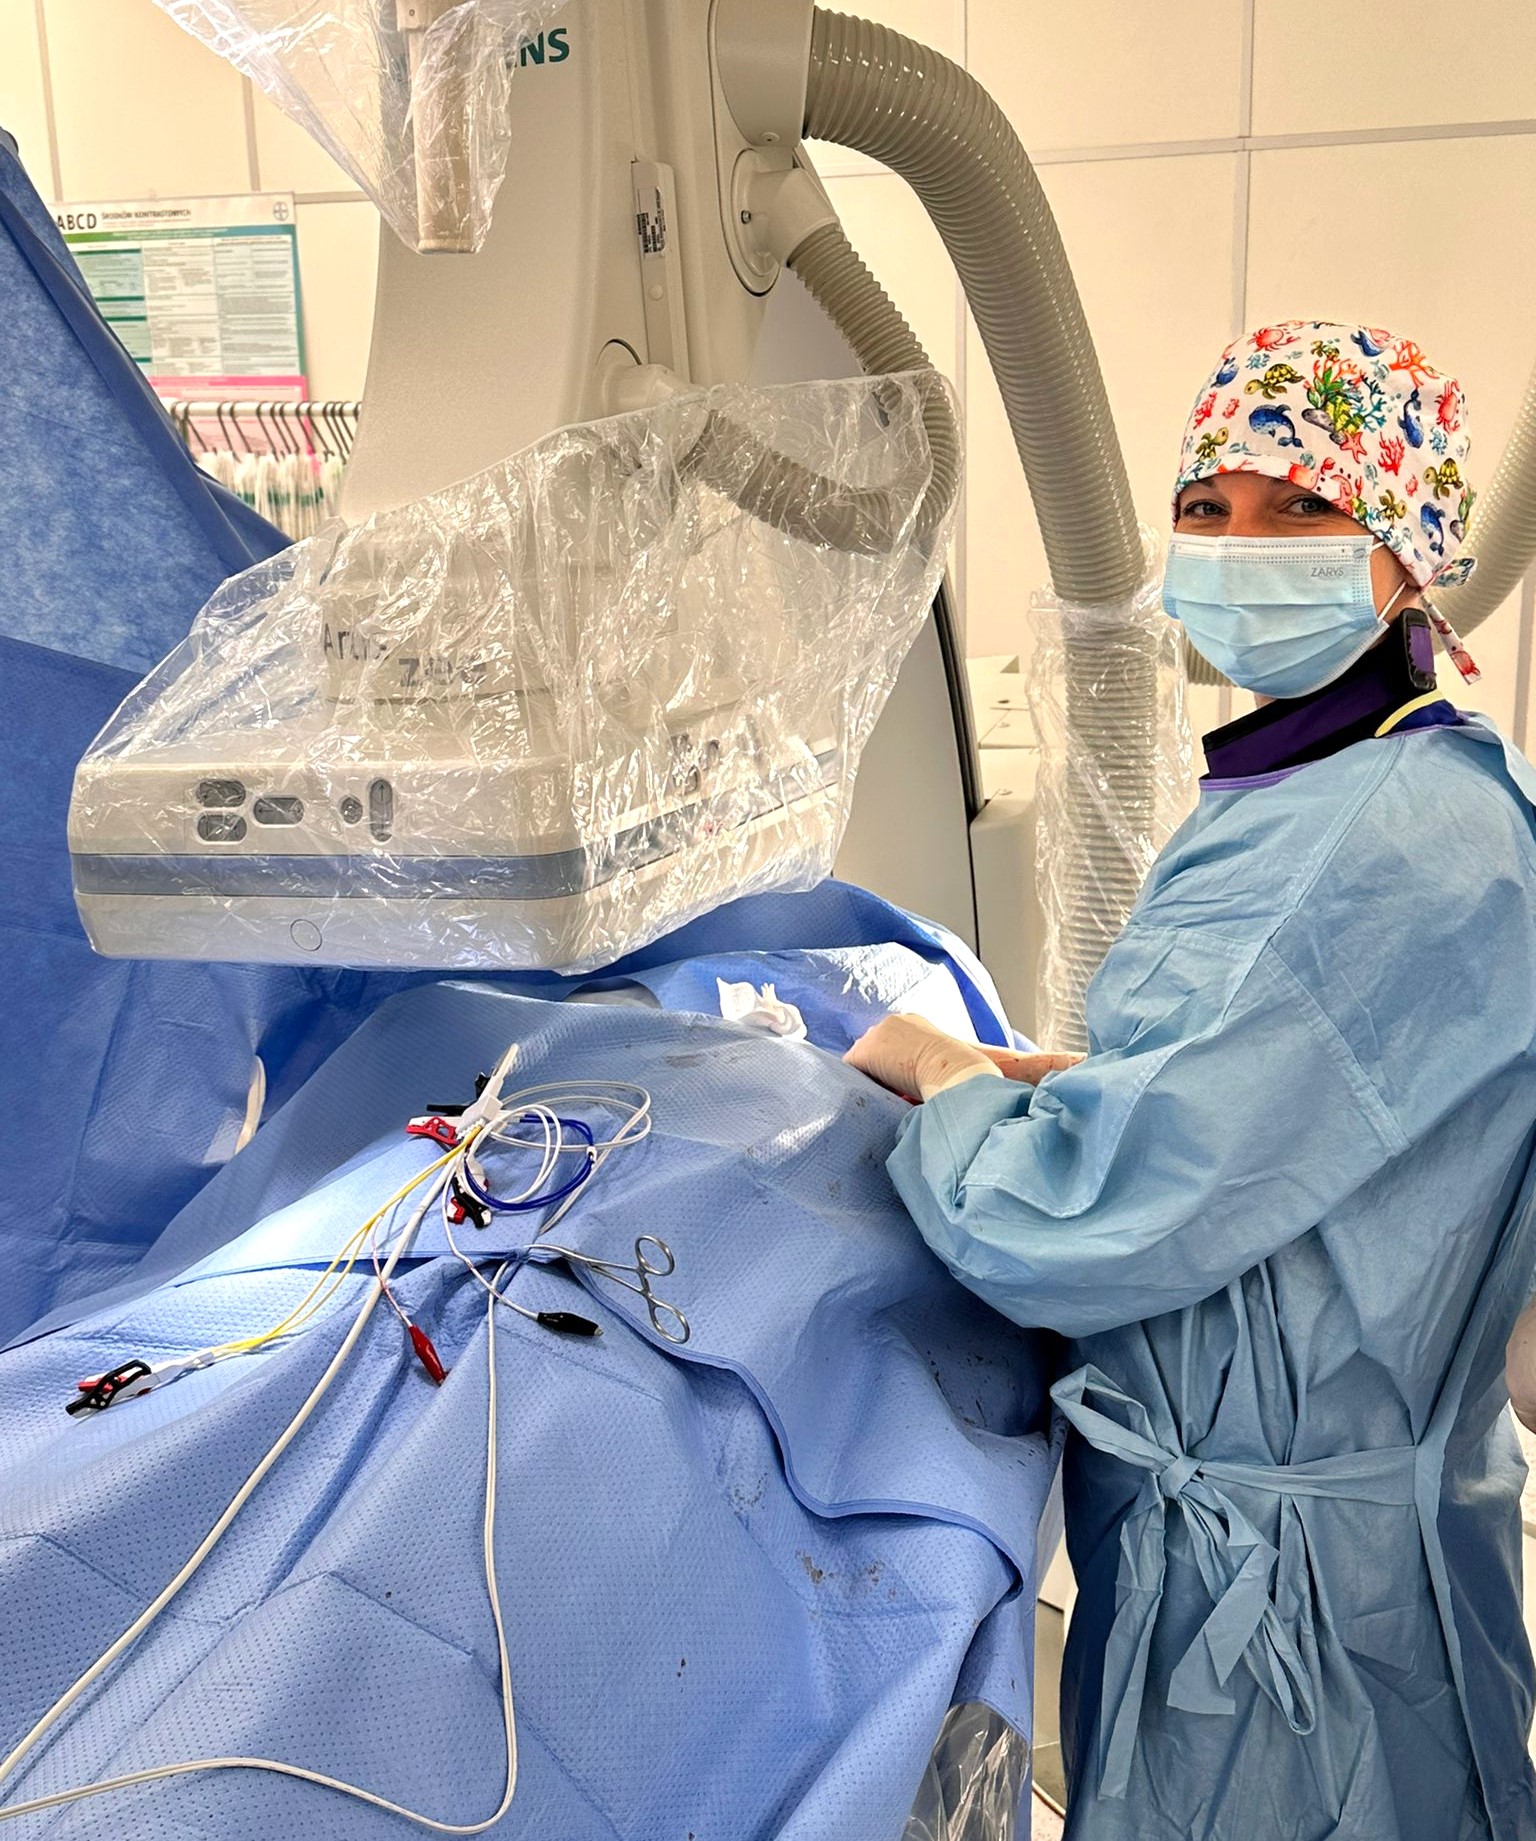

fot. Szpital Miejski nr 4 w Gliwicach

W Gliwicach wszczepiono rozrusznik serca z najnowocześniejszym typem stymulacji

Opublikowane: 27.05.2024 / Sekcja: Miasto ZdrowieWyjątkowość zabiegu przeprowadzonego przez zespół kardiologów Szpitala Miejskiego nr 4 polegała na tym, że pacjentowi wszczepiono elektrodę nie do koniuszka prawej komory serca, lecz do lewej odnogi pęczka Hisa. Dzięki temu impuls wytwarzany przez supernowoczesny rozrusznik serca, generujący skurcze przedsionków i komór, rozchodzi się najbardziej fizjologiczną z możliwych dróg.